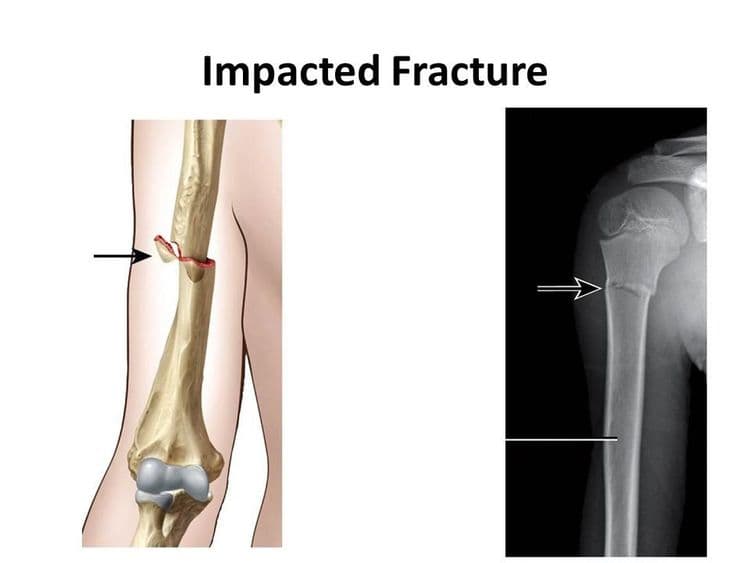

Impacted Fracture - एखादे हाड तुटते तेव्हा त्या हाडाचा हिस्सा दुसऱ्या हाडांमध्ये घुसण्याची स्थिती.